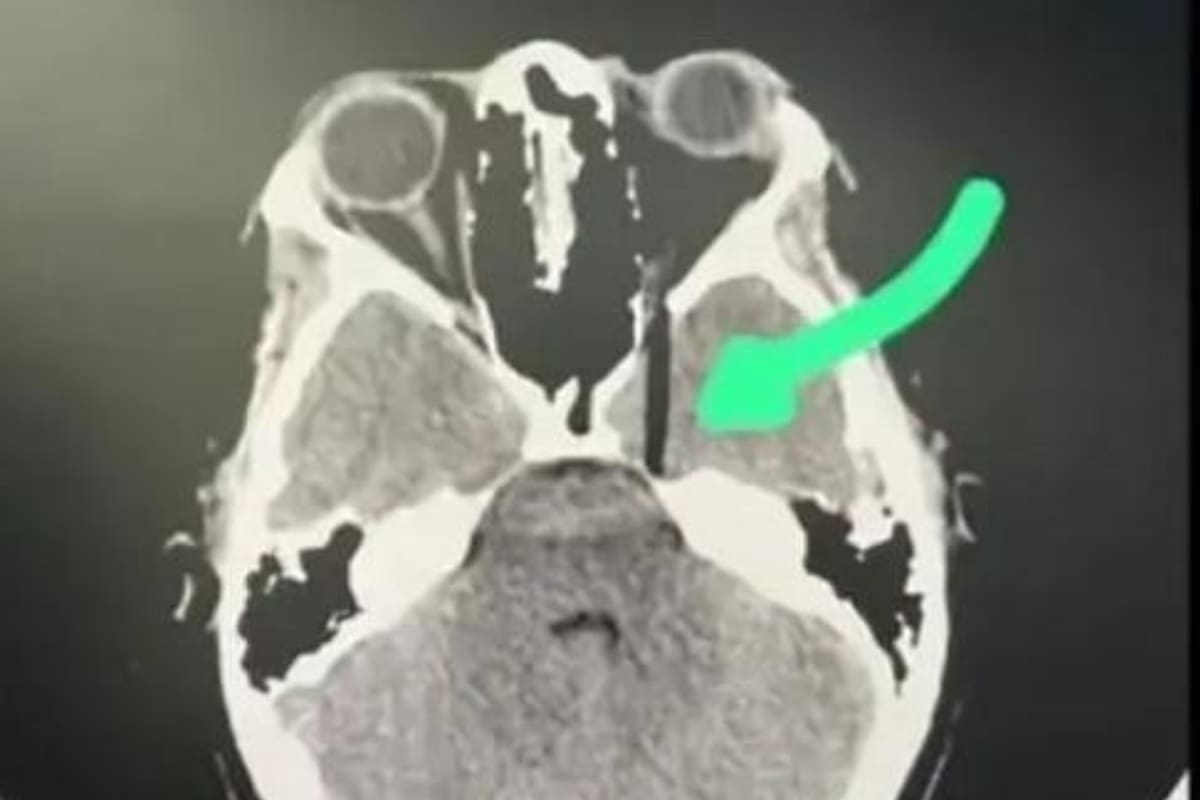

Además de estas declaraciones, también circuló una imagen correspondiente a una tomografía en donde se puede observar como se incrustó el palo en el ojo de la víctima. En redes sociales, frecuentemente aparecen recomendaciones de especialistas médicos o de pastelería que piden no realizar estas bromas, justamente por precaución de que no haya algo en el interior de la torta que actúe como soporte.

Al llevar a cabo esta acción, la homenajeada se clavó un palo de madera en uno de sus ojos. Como consecuencia de esto, tuvo que recibir tratamiento médico y estuvo cerca de sufrir daño cerebral.